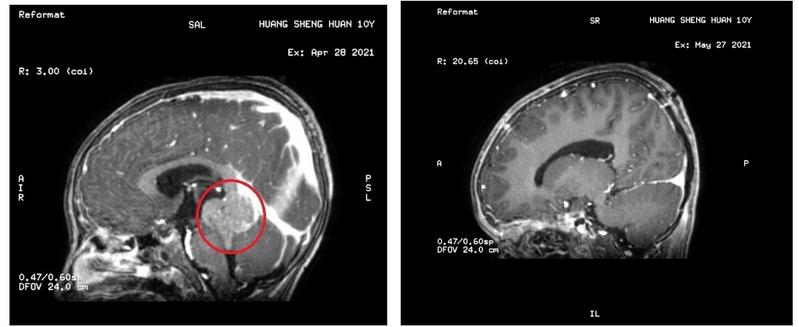

孩子持续头晕、呕吐,别不在意。湛江10岁的小乐(化名)“感冒”了一个月,结果在医院检查才发现是颅内深部长了个直径4-5cm大肿瘤,并伴有重度脑积水,确诊为“第三脑室及松果体区生殖细胞瘤”。

家长带小乐到大医院做检查,这一检查彻底打乱了这个家庭的生活。小乐被查出颅内深部长了个直径4-5cm的大肿瘤,并伴有重度脑积水。小乐父母急忙带小孩到广州寻求治疗。

方案敲定并完善相关术前检查后,4月28日为小乐进行“右侧脑室穿刺引流术”,术后小乐头晕、呕吐症状明显缓解;4月30日在全麻下进行“后正中入路第三脑室及松果体区巨大肿瘤切除术”,手术顺利完成。术后病理结果为生殖细胞瘤。目前,小乐已接受放疗和化疗,恢复良好。

治疗前后,颅内肿瘤(红圈处)消失